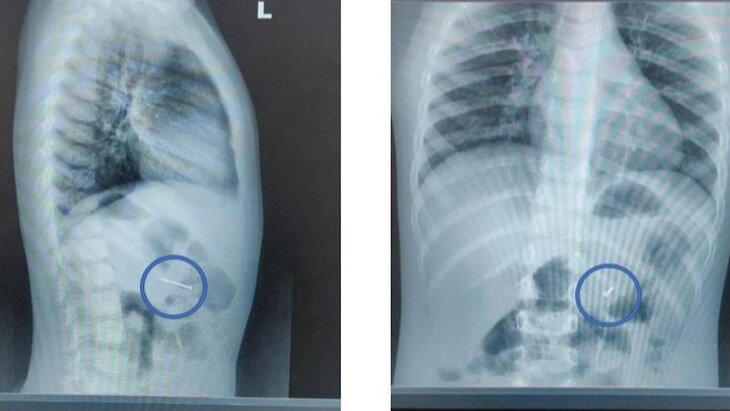

Сначала специалисты сделали рентген, который подтвердил наличие гвоздя в желудке. Затем с помощью эндоскопических щипцов они захватили предмет за острый конец и вытащили через рот. Процедура заняла около 20 минут, отметил Мусаев.